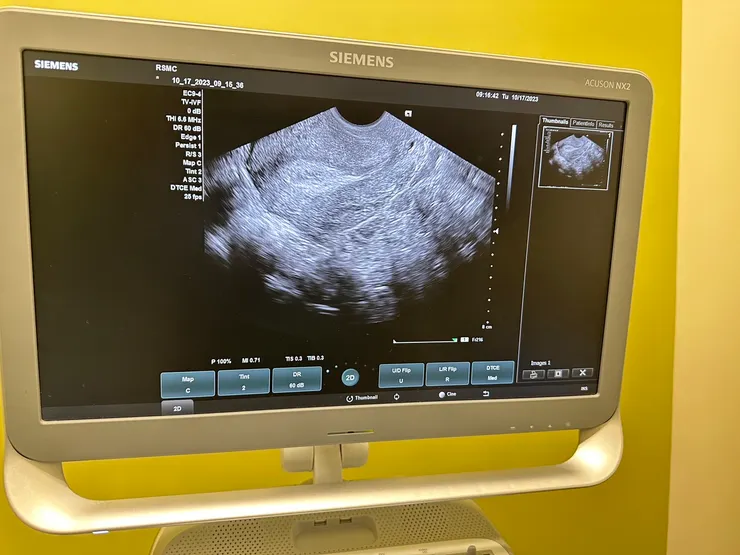

第三階段的用藥,就是針劑孕酮加上塞劑孕酮,以及抗生素和皮質酮的用藥,是為了植入前做準備的,所以在第三次的回診,也算是最重要的一次了,前面回診主要只有以抽血為主,但在第三次回診時就加上了陰道超音波了!看起來女友對於雌二醇的反應相當良好,在檢查子宮內膜的厚度時,這時候已經長到12.6了,黃金三條線的部分也看得非常清楚,我們都笑稱不知不覺都已經長好了一個豪宅了呢!也因為對於雌二醇的反應良好,所以在這四次的打針中,女友的雌二醇從一開始的0.2ml降到0.1ml(不過也才打四次而已),但她一直說是不是因為她吃酪梨的關係!

傳說中的黃金三條線,寶寶的豪宅